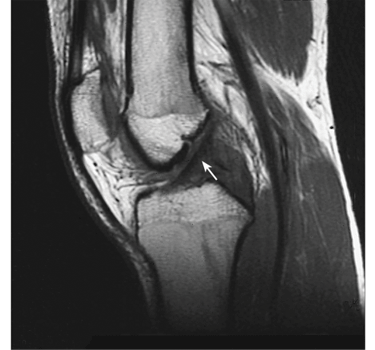

Appropriate Medically Acceptable Imaging Techniques

An imaging technique, such as X-ray or MRI (see Figure 8 below), should show joint abnormalities. The technique should be “appropriate.” For example, a plain X-ray might be sufficient to rule out a bony arthritic process, but would not show soft tissue damage (e.g., fibrous ankylosis) that would be visible on a MRI. The listing specifically requires evidence of joint involvement (“joint space narrowing, bony destruction, or ankylosis”), whether or not there is soft tissue damage resulting in instability. This is a critical point because a purely soft-tissue injury such as damage to knee ligaments in a sports or other acute injury, even if unrepaired surgically and producing abnormal motion, would still fail to satisfy the listing because there would be no joint involvement as required in the imaging specifications. On the other hand, fibrous ankylosis of a joint could qualify as a gross deformity under the listing even though there is no direct bony damage to the joint.

Figure 8: An MRI image of a normal knee.